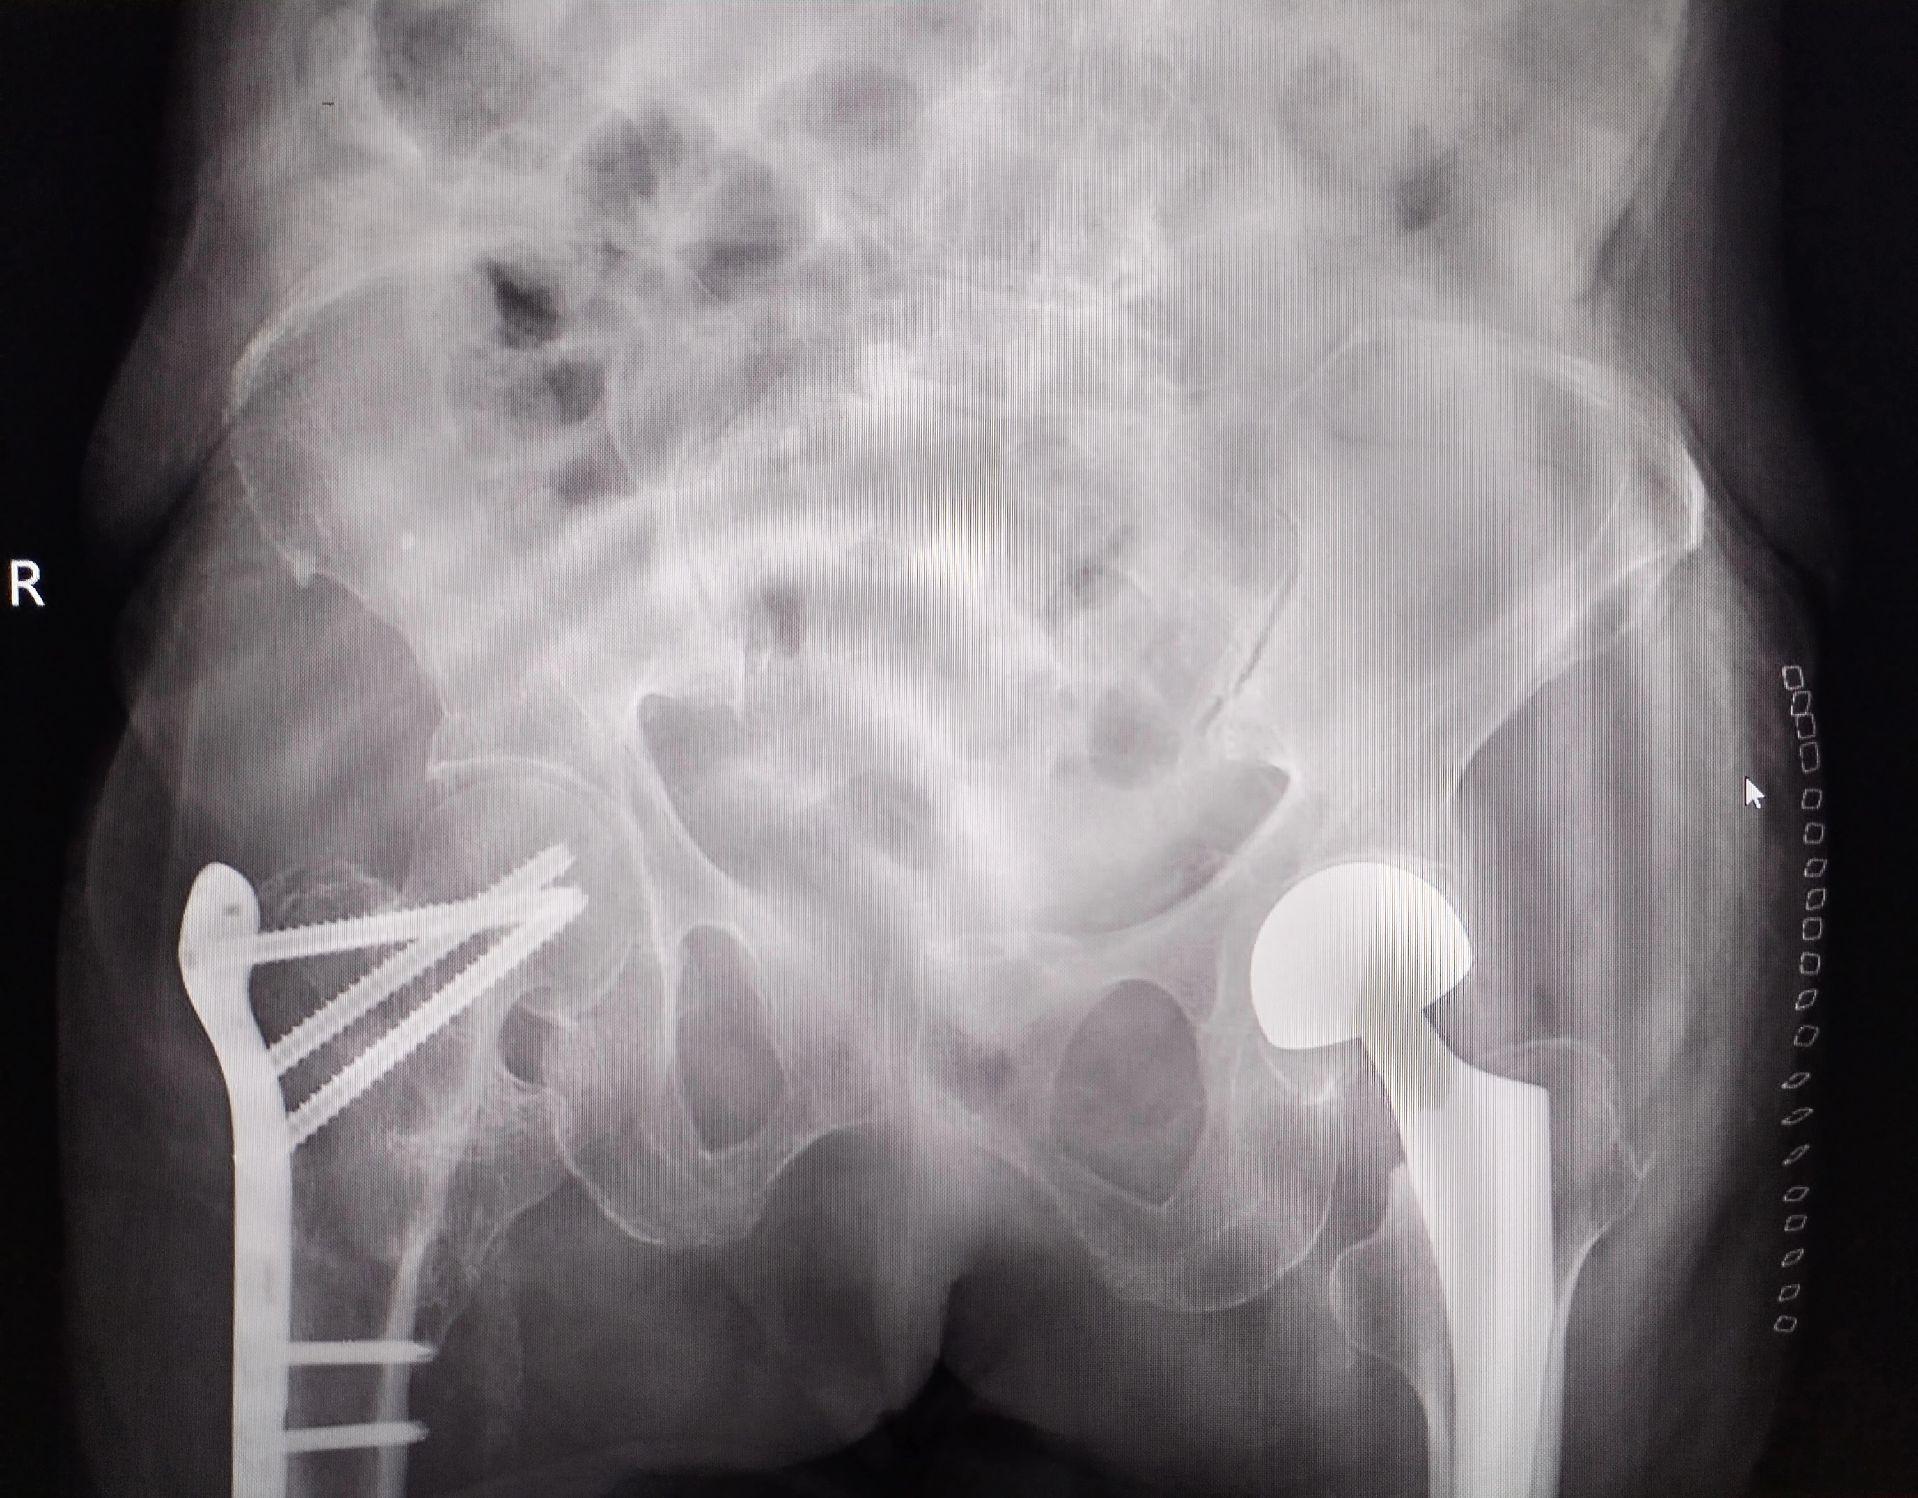

股骨颈骨折。101岁老太太,股骨颈骨折,鬼门关走一遭又回来了。家属的充分理解和支持,相关科室的齐心协力,是手术成功的关键因素🌹髋关节置换

股骨颈骨折。101岁老太太,股骨颈骨折,鬼门关走一遭又回来了。家属的充分理解和支持,相关科室的齐心协力,是手术成功的关键因素🌹